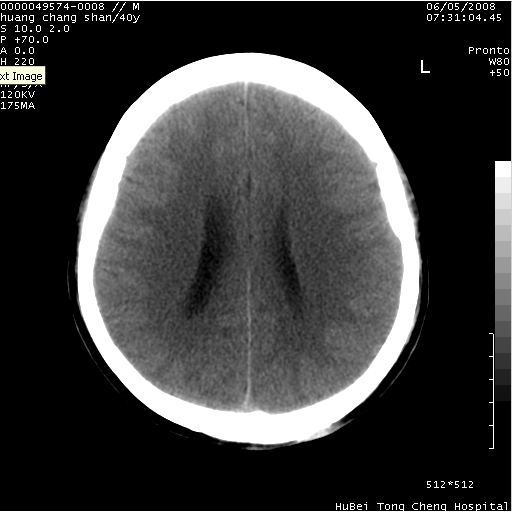

患者 m,40y。头痛,视力模糊,多饮多尿,性欲减退半年余。

行ct平扫+增强,图象如下:

肿瘤强化明显、鞍部骨质结构未见增大、破坏,考虑脑膜瘤可能性大

鞍背无破坏和明显受压,病变明显均匀强化,边界清晰。鞍上区脑膜瘤可能性大,不除外生殖细胞瘤。

平扫病灶呈等密度,增强后强化明显,均匀一致,结合病史首先考虑:垂体瘤。脑膜瘤不支持,因为脑膜瘤平扫多为实性呈均匀高密度影像,内分泌症状多不明显,垂体内分泌素测定正常。

鞍上池肿瘤,鞍背及垂体窝形态变化不明显,病灶强化密度均匀且高度强化,考虑实性颅咽管瘤、生殖细胞瘤及脑膜瘤可能。

结合临床考虑鞍上生殖细胞瘤可能性大于脑膜瘤(增强未见脑膜围征),建议结合冠状位扫描看病灶起源及垂体窝、鞍底情况。垂体窝内未见明显软组织密度影,垂体窝未见扩大,暂不考虑垂体瘤;病灶较大,未见囊变及钙化,颅咽管瘤不支持。期待结果!

1、头痛,视力模糊,多饮多尿,性欲减退半年余,提示:肿瘤为功能性肿瘤。

2、ct表现:肿瘤呈类圆形,均匀略高密度,无囊变,无钙化。侧脑室有扩大。

3、首先考虑:功能性垂体大腺瘤。

4、鉴别诊断:脑膜瘤,瘤体内点状钙化最具特征性,常位于鞍结节。颅咽管瘤,蛋壳样钙化,常有囊变。动脉瘤,位于鞍旁,强化与动脉一致。有时尚需与发生于鞍区的生殖细胞瘤鉴别,生殖细胞瘤钙化亦较常见。

5、友情提示:下回发现鞍区占位性病变,最好加扫冠状位,了解肿瘤与蝶鞍的关系及蝶鞍骨质的改变。